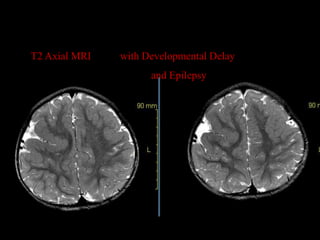

T2 Axial MRI   with Developmental Delay

and Epilepsy

T2 Axial MRI with Developmental Delay and Epilepsy